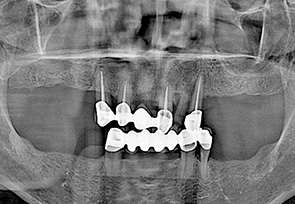

before

after